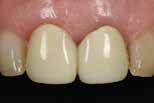

Porcelain veneers are ultra-thin, shell-like layers of dental porcelain that are placed directly on the outside of the existing teeth. In order to apply the veneer, a tiny amount of the tooth’s surface is removed (usually less than 1mm) so that the veneer sits flush with the rest of the teeth. This not only allows for better aesthetics but also helps the natural function of the tooth.

Minimal preparation veneers are a great treatment for anyone who is discontent with their smile, and looking for a long-term solution that requires very little maintenance. It is also a great treatment for someone who wants a straighter and more even smile without having to wear braces. As the treatment requires very minimal preparation, there is virtually no damage to the patient’s natural teeth unlike you see in the renowned ‘Turkey Teeth’ smile makeovers.

In this particular smile makeover, the patient was unhappy with her old, discoloured veneers and wanted to replace them with fresh ones. We fitted twelve veneers on her upper arch, which has given her a beautifully balanced, brighter natural looking smile.

If you would like to know more about minimal prep porcelain veneers, or if you would like to explore other treatments we offer, then call us on 0161-486-0743 and book in for your complementary consultation at our multi-award winning, state of the art dental clinic today.

Smile Makeover Using Minimal Prep Porcelain Veneers

Cheadle Hulme Dental & Cosmetics, 20a Station Road, Cheadle Hulme, SK8 7AB